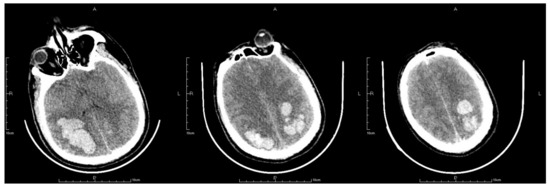

On the second postoperative day, the patient presented with idiopathic unconsciousness, limb twitching, and trismus. An emergency cranial CT scan demonstrated scattered hemorrhages in the bilateral frontoparietal lobes along with subarachnoid hemorrhages and edematous zones around some lesions (Figure 2 and Figure 3). Following an emergency consultation with the Department of Neurology and Neurosurgery, a diagnosis of venous sinus thrombosis combined with multi-focus cerebral hemorrhage was made. As per their orders, the patient underwent an emergency interventional intracranial angiography and thrombectomy.

Figure 2.

The letter R, A, P, L in the figures refers to Right, Anterior, Posterior and Left, respectively. Emergency CT scan showed scattered hemorrhages in bilateral frontoparietal lobes combined with subarachnoid hemorrhage and edema zones around some lesions (a–c).